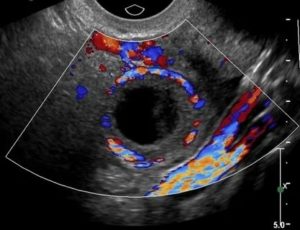

Киста желтого тела

Иногда в структуре желтого тела появляются большие (до 7-8 см) полости, заполненные серозной жидкостью или сгустками крови. Эти полости хорошо заметны на УЗИ и называются кистами желтого тела.

На УЗИ киста желтого тела смотрится достаточно «устрашающе», хотя для жизни и здоровья женщины абсолютно не опасна.

Поскольку полость кисты заполнена свернувшейся кровью и нитями фибрина, структура ее крайне разнообразна и требует тщательной диагностики. Такие кисты даже опытные врачи часто путают со злокачественными опухолями яичника.

Как выглядит киста

Диагностируют кисту (жидкостную полость) желтого тела на УЗИ при размере железы больше 3 см с одновременным появлением черного пятна без светлых вкраплений. Это образование на зачатие и беременность не влияет, может само регрессировать (исчезнуть). Женщину наблюдают 3 месяца. В случае быстрого роста кисты начинают лечение.